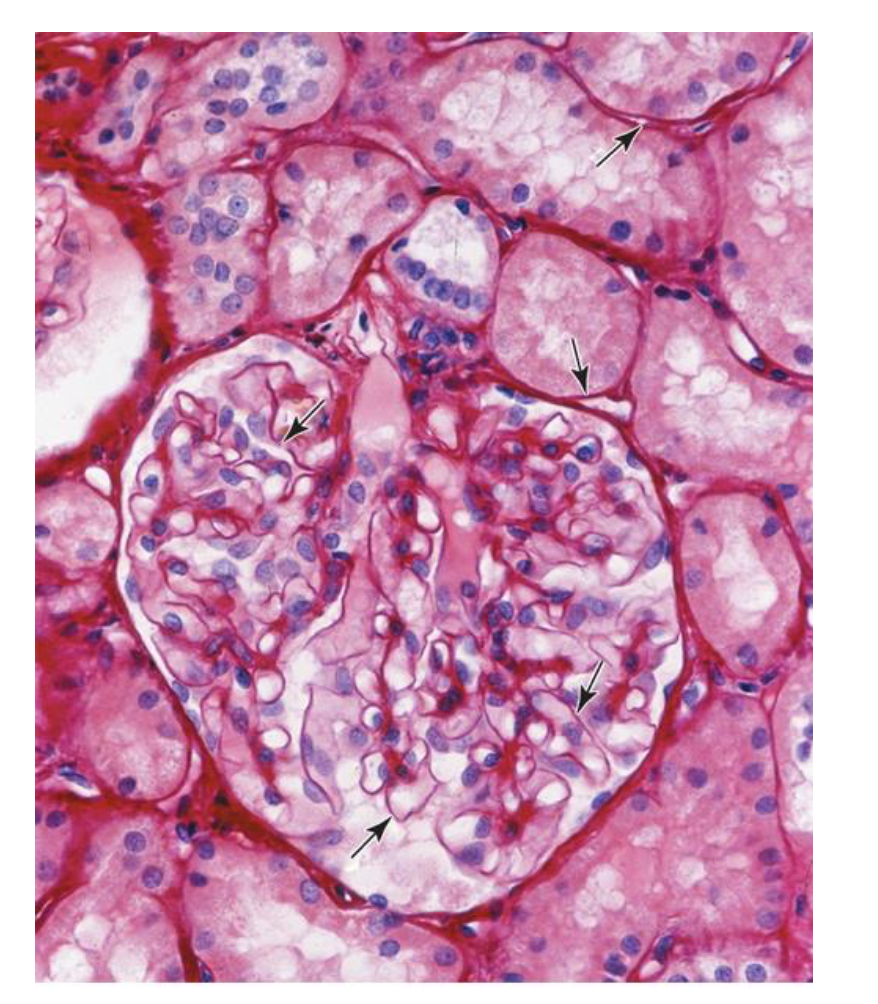

How do you classify tissue type?

simple squamous

simple cuboidal

simple columnar